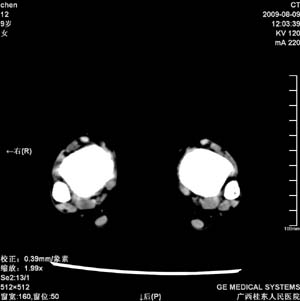

标题: PED2867:右侧内踝肿胀,骨质改变,请各位老师会诊 [打印本页]

标题: PED2867:右侧内踝肿胀,骨质改变,请各位老师会诊

九岁小朋友,近期左侧内踝疼痛,局部肿胀,平时无特殊,近期经常溜干冰

对不起,是右侧内踝肿胀

双踝关节骨质及发育未见异常。

左侧内踝密度增高,请结合临床!